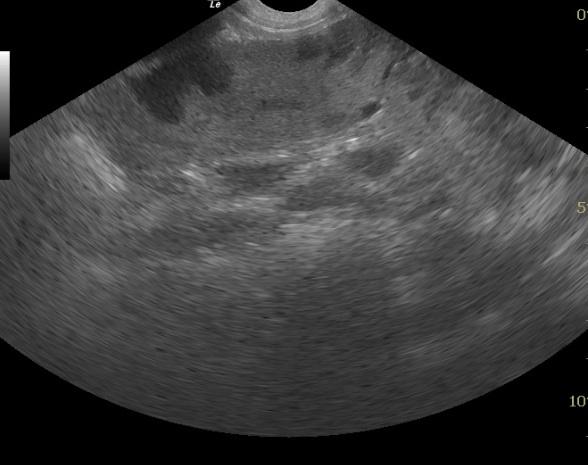

The spleen was heterogenous with mixed hypoechoic nodular or cavitated lesions and areas of capsular expansion. No evidence of rupture was noted. However, a mass is present at the caudal splenic body.

SplenicabcessSplenicabcessSplenicabcess